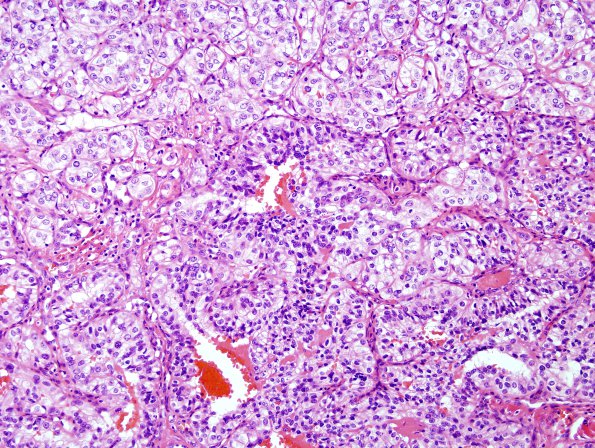

Washington University Experience | NEOPLASMS (METASTASES) | Microscopic | 38A2 Metastasis, renal cell CA (Case 38) H&E 1

38A2 Metastasis, renal cell CA (Case 38) H&E 1

Sections show metastatic clear cell carcinoma (H&E)